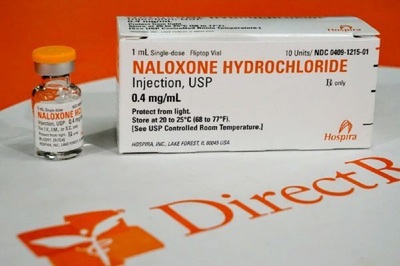

Diplomat Pharmacy to dispense opioid-overdose drug

Diplomat Pharmacy Inc. recently announced that it will dispense opioid-overdose antidote naloxone without prescription to residents in Michigan via the company’s retail pharmacy at G-3320 Beecher Road in Flint. Read More »